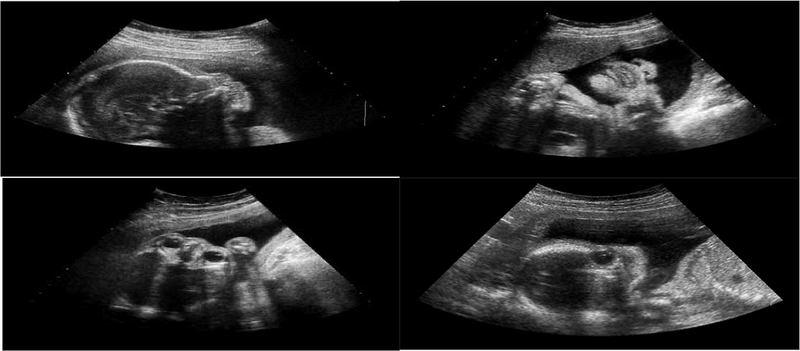

Giấy siêu âm thai nhi 3 tuần tuổi có những thông tin gì? 1

Thai nhi được tạo thành từ hợp tử giữa trứng và tinh trùng

Giấy siêu âm thai nhi 3 tuần tuổi có những thông tin gì? 2

Giấy siêu âm thai nhi 3 tuần tuổi giúp xác định vị trí của thai nhi trong tử cung